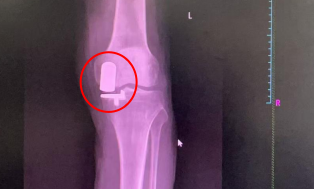

▲膝关节单髁置换术前术后 保留健康组织的治疗理念 膝关节单髁置换术通过微创技术仅置换病变严重的单侧间室(内侧或外侧),这种“精准定位”的治疗方式,能够尽可能保留患者健康的骨组织、韧带及本体感觉,手术创伤相对较小。术后患者疼痛可得到缓解,膝关节的自然活动功能得以保留,步态恢复更趋向自然协调。 多学科协作优化恢复流程 快速康复外科理念贯穿于治疗全程,为患者提供标准化、个性化的康复路径。术前进行全面评估和健康宣教,帮助患者做好身心准备;术中采用精细化操作,减少组织损伤;术后早期康复师介入指导功能锻炼。这种多学科协作模式有助于缩短住院时间,多数患者能在短期内达到出院标准,更快回归家庭生活。 护理团队实施全程化健康管理,从入院到出院后随访,提供涵盖疾病知识、康复锻炼、居家护理等全方位指导。针对患者术后可能出现的心理压力,医护人员可提供专业心理疏导,帮助建立积极康复的信心。 个性化方案助力功能恢复 膝关节功能的良好恢复,离不开科学系统的康复训练。专业医疗团队会为患者量身定制康复计划:早期进行关节活动度训练,防止粘连;中期强化肌力训练,增强关节稳定性;后期优化步态训练,提升活动协调性。通过循序渐进的康复锻炼,多数患者能够恢复日常活动能力,完成行走、上下楼梯等动作。 微创技术的临床应用优势 膝关节单髁置换术的临床应用特点包括:手术切口较小,术后疼痛轻,恢复时间短;保留更多自身组织,关节活动更接近自然状态;术后并发症风险低,康复效果稳定。临床实践中,患者在疼痛缓解、关节功能恢复及生活质量改善等方面可获得良好反馈。 健康提醒 当膝关节疼痛严重影响生活质量时,及时寻求专业医疗帮助至关重要。通过精准微创技术、快速康复流程和个性化护理方案,膝关节单髁置换术为患者提供了一种重获行动自由的可能。科学应对膝关节炎,才能让生活回归轻盈与活力。 关节骨病科简介 基本概况 我院关节骨病科现开放床位32张,汇聚了16名经验丰富、技术精湛的专业医护人员。科室以关节疾病诊疗、运动医学修复、骨病外科治疗为核心发展方向,深耕骨关节疾病、运动损伤、病理性骨折及骨科肿瘤等领域,为患者提供全方位、个性化的精准医疗服务。 诊疗技术 关节置换与翻修:早期股骨头坏死保髋术,人工股骨头/全髋关节置换术,髋关节翻修术,膝关节单髁置换/表面置换术,膝关节翻修术,人工肩关节置换术。 关节镜微创技术:关节镜下膝关节前后交叉韧带重建术,半月板缝合/成形术,关节内骨折镜下复位内固定术,肩袖修复术,肩关节不稳修复术,肩峰成形术,踝关节镜下韧带修复重建术。 骨肿瘤综合治疗:四肢骨肿瘤切除重建(含关节置换),骨肿瘤保肢术、化疗术。 其他骨病治疗:骨结核病灶清除植骨术,同种异体骨移植,各类病灶清除术,肢体矫形修复术。 专家简介 周仁实 主任医师、副院长。 1996广东医科大学临床医学本科毕业,从事骨科临床工作20多年。发表SCI论文1篇(通信作者),国家级省级论文10多篇。社会兼职:广东省医学教育委员会脊柱专业委员会副主任委员,广东省医师协会理事等。 擅长领域:擅长脊柱内固定、脊柱微创、骨肿瘤、关节置换、关节镜等技术,熟悉掌握骨科常见病与多发病的诊断与治疗。 欧阳思强 骨外科主任医师,关节骨病科主任。 广东省医师协会骨关节外科医师分会委员。2003年毕业于广东医学院临床医学系,毕业后一直从事骨科工作,曾先后到南方医科大学附属南方医院、广东省中医院进修。 擅长领域:擅长关节、骨病,运动损伤等疾病的诊断治疗;熟练掌握人工关节置换、人工关节翻修、骨关节病治疗,以及运动损伤疾病的关节镜下手术治疗等。 李远志 中西医结合医学副主任医师,关节骨病科副主任,硕士研究生学历。 2009年毕业于福建中医药大学,曾先后到河南省洛阳正骨医院、广州中医药大学一附院骨关节病科进修学习。 擅长领域:擅长关节、脊柱、骨病等中西医结合治疗。 黄平 骨外科主任医师。 曾到广州南方医学院创伤骨科进修学习。 擅长领域:擅长骨关节病、骨肿瘤的诊治;熟练掌握各类长骨骨折手法复位及切开复位内固定治疗术,骨盆骨折切开复位内固定术、断肢再植术、各类创面修复术;能主刀完成人工全髋关节置换、人工膝关节表面置换手术,掌握了髋关节、膝关节翻修技术。 苏中南 骨科主治医师。 2012年毕业于三峡大学临床医学系。曾到暨南大学附属第一医院进修学习关节、运动医学专业。 擅长领域:熟悉人工关节置换、关节镜的检查和治疗,擅长关节、骨病、运动损伤、脊柱等常见病与多发病的诊断与治疗。 王德信 中医骨伤主治医师,研究生学历。 擅长领域:熟练掌握四肢骨折正骨、运动创伤、大面积烧伤、慢性溃疡创面修复处理、关节脱位整复,四肢骨关节疾病诊治。熟悉应用内固定及外固定技术治疗各种常见骨折,能运用中西医结合、辩证运用方剂保守治疗股骨颈骨折、股骨头缺血性坏死、风湿、类风湿关节炎、髋膝关节骨关节病、老年性骨质疏松等关节骨病科常见疾病。